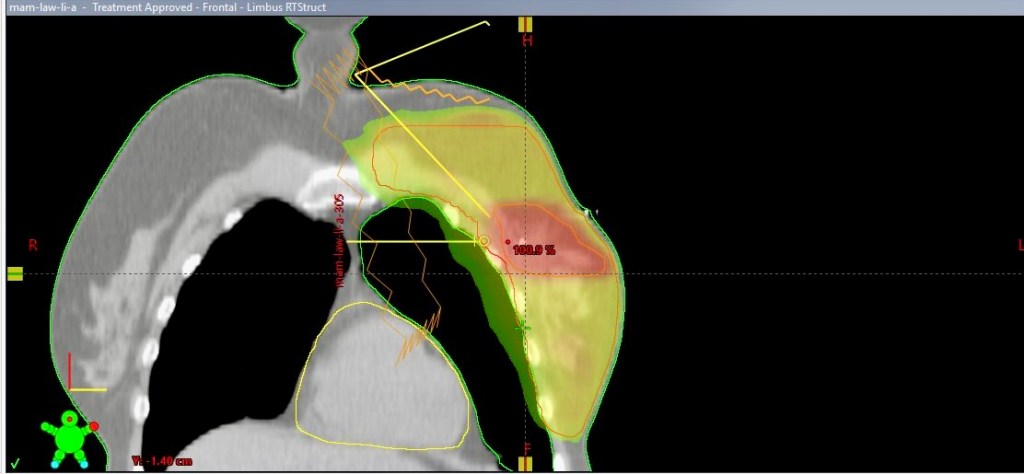

Passgenau im allerengsten Sinne

Für die spätere Strahlenbehandlung werden im Vorfeld Bereiche und Winkel festgelegt und so passgenau berechnet, wie man es sich kaum vorstellen kann. Er zeigt mir das anhand meiner eigenen Bilder und als wir nach einer ganzen Weile unterbrochen werden, sagt er: „An dieser Stelle wurden erst zwei Tage lang Berechnungen für dich gemacht. Da kommt noch mehr als die doppelte Zeit dazu.“, meint Dr. Koppe und fügt hinzu: „Ein weiterer sehr wichtiger Vorgang ist, nach all der Rechnerei und noch lange bevor wir unsere Patientinnen und Patienten mit den Strahlen behandeln, dass wir zum Einen, so wie es auch bei den Tumorkonferenzen ist, zusammensitzen und nach dem Vier-Augen-Prinzip gemeinsam mit Technikern und Kollegen beraten, ob der Behandlungsplan zu 100 % stimmig ist. Zum Anderen erstellen wir, bevor wir die Leute bestrahlen, auf dem Bestrahlungsuntergrund in einem Probedurchlauf mit dem Gerät eine Art Blaupause. Dabei entsteht beispielsweise dein ganz individuelles Behandlungsmuster. Dieses Vorgehen sichert noch ein weiteres Mal ab, dass du genau die Behandlung bekommst, die du benötigst. Nicht mehr und nicht weniger.“